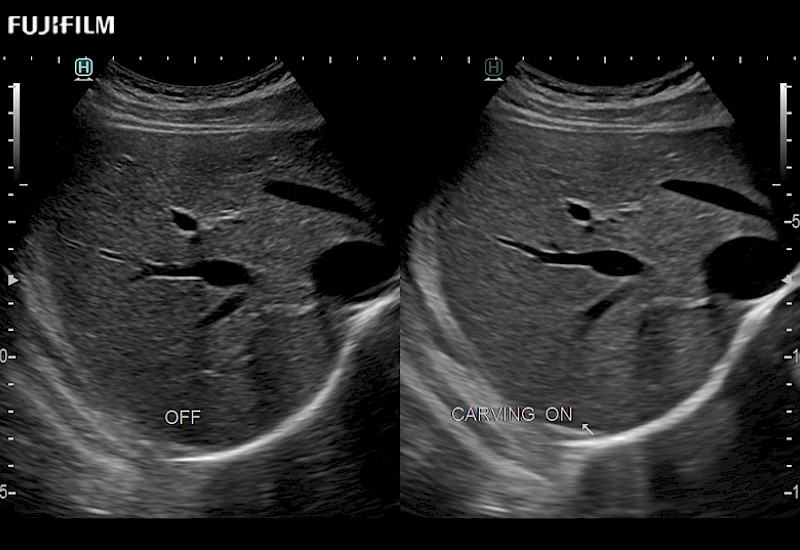

Extraordinary high-resolution digital imaging

Multi-Parametric imaging modalities

Fully customizable

to meet specific needs

The ARIETTA 750 incorporates all of the proven technologies and functions that medical professionals have come to expect from Fujifilm Healthcare.

ARIETTA 750 is the definitive diagnostic ultrasound solution for any clinical setting - Private Office, Imaging Center, or Hospital. The ARIETTA platform provides the ultimate in clinical performance with its state-of-the-art features and large user-friendly display.

The ARIETTA 650 DI combines trusted Fujifilm Healthcare technologies and features tailored for surgical oncology.

Designed to meet the demands of surgeons, the ARIETTA 650 DI offers precise guidance. Its advanced capabilities and large, intuitive display offer accurate and efficient care in operating rooms and specialized surgical settings.

Fujifilm Healthcare continues to listen to the experts, our neurosurgeons, by developing an ultrasound system specifically designed for the Operating Room.

Guidance is the fundamental purpose for all of our surgical ultrasound technology. Fujifilm Healthcare is committed to designing tools that help neurosurgeons navigate inside the human body and provide the necessary information to immediately make critical surgical decisions.

With the ARIETTA Precision the next level of surgical ultrasound is here.